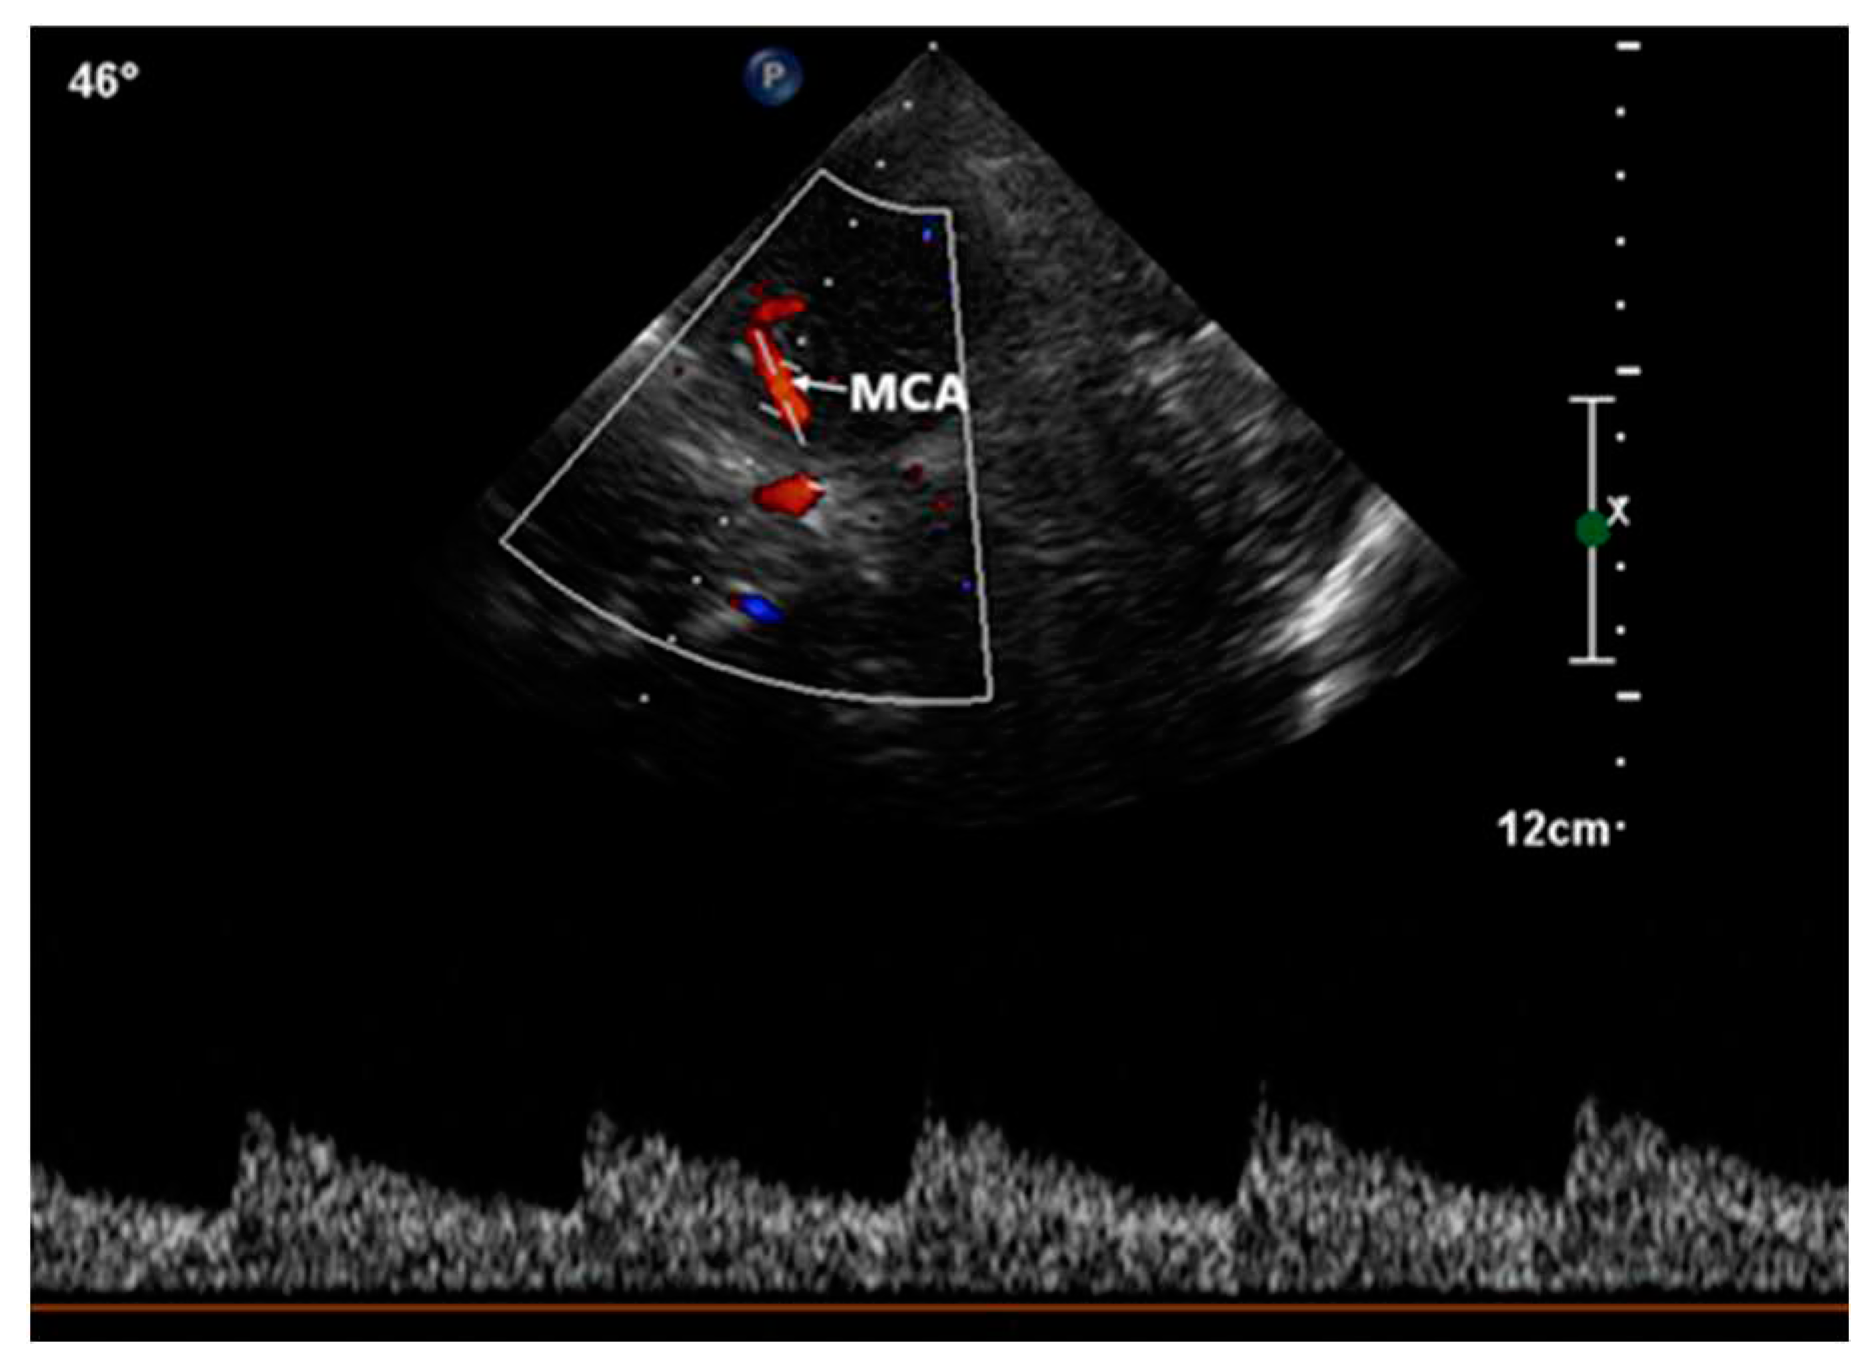

This procedure was facilitated by imaging through the squamous section of the temporal bone. The detection of high-intensity transient signals (HITS), which indicate the presence of microbubbles, was conducted by assessing the middle segment of the right middle cerebral artery using TCCD (Figure 4).

Figure 4. Transcranial color-coded doppler with pulsedwave spectral doppler of the middle cerebral artery.